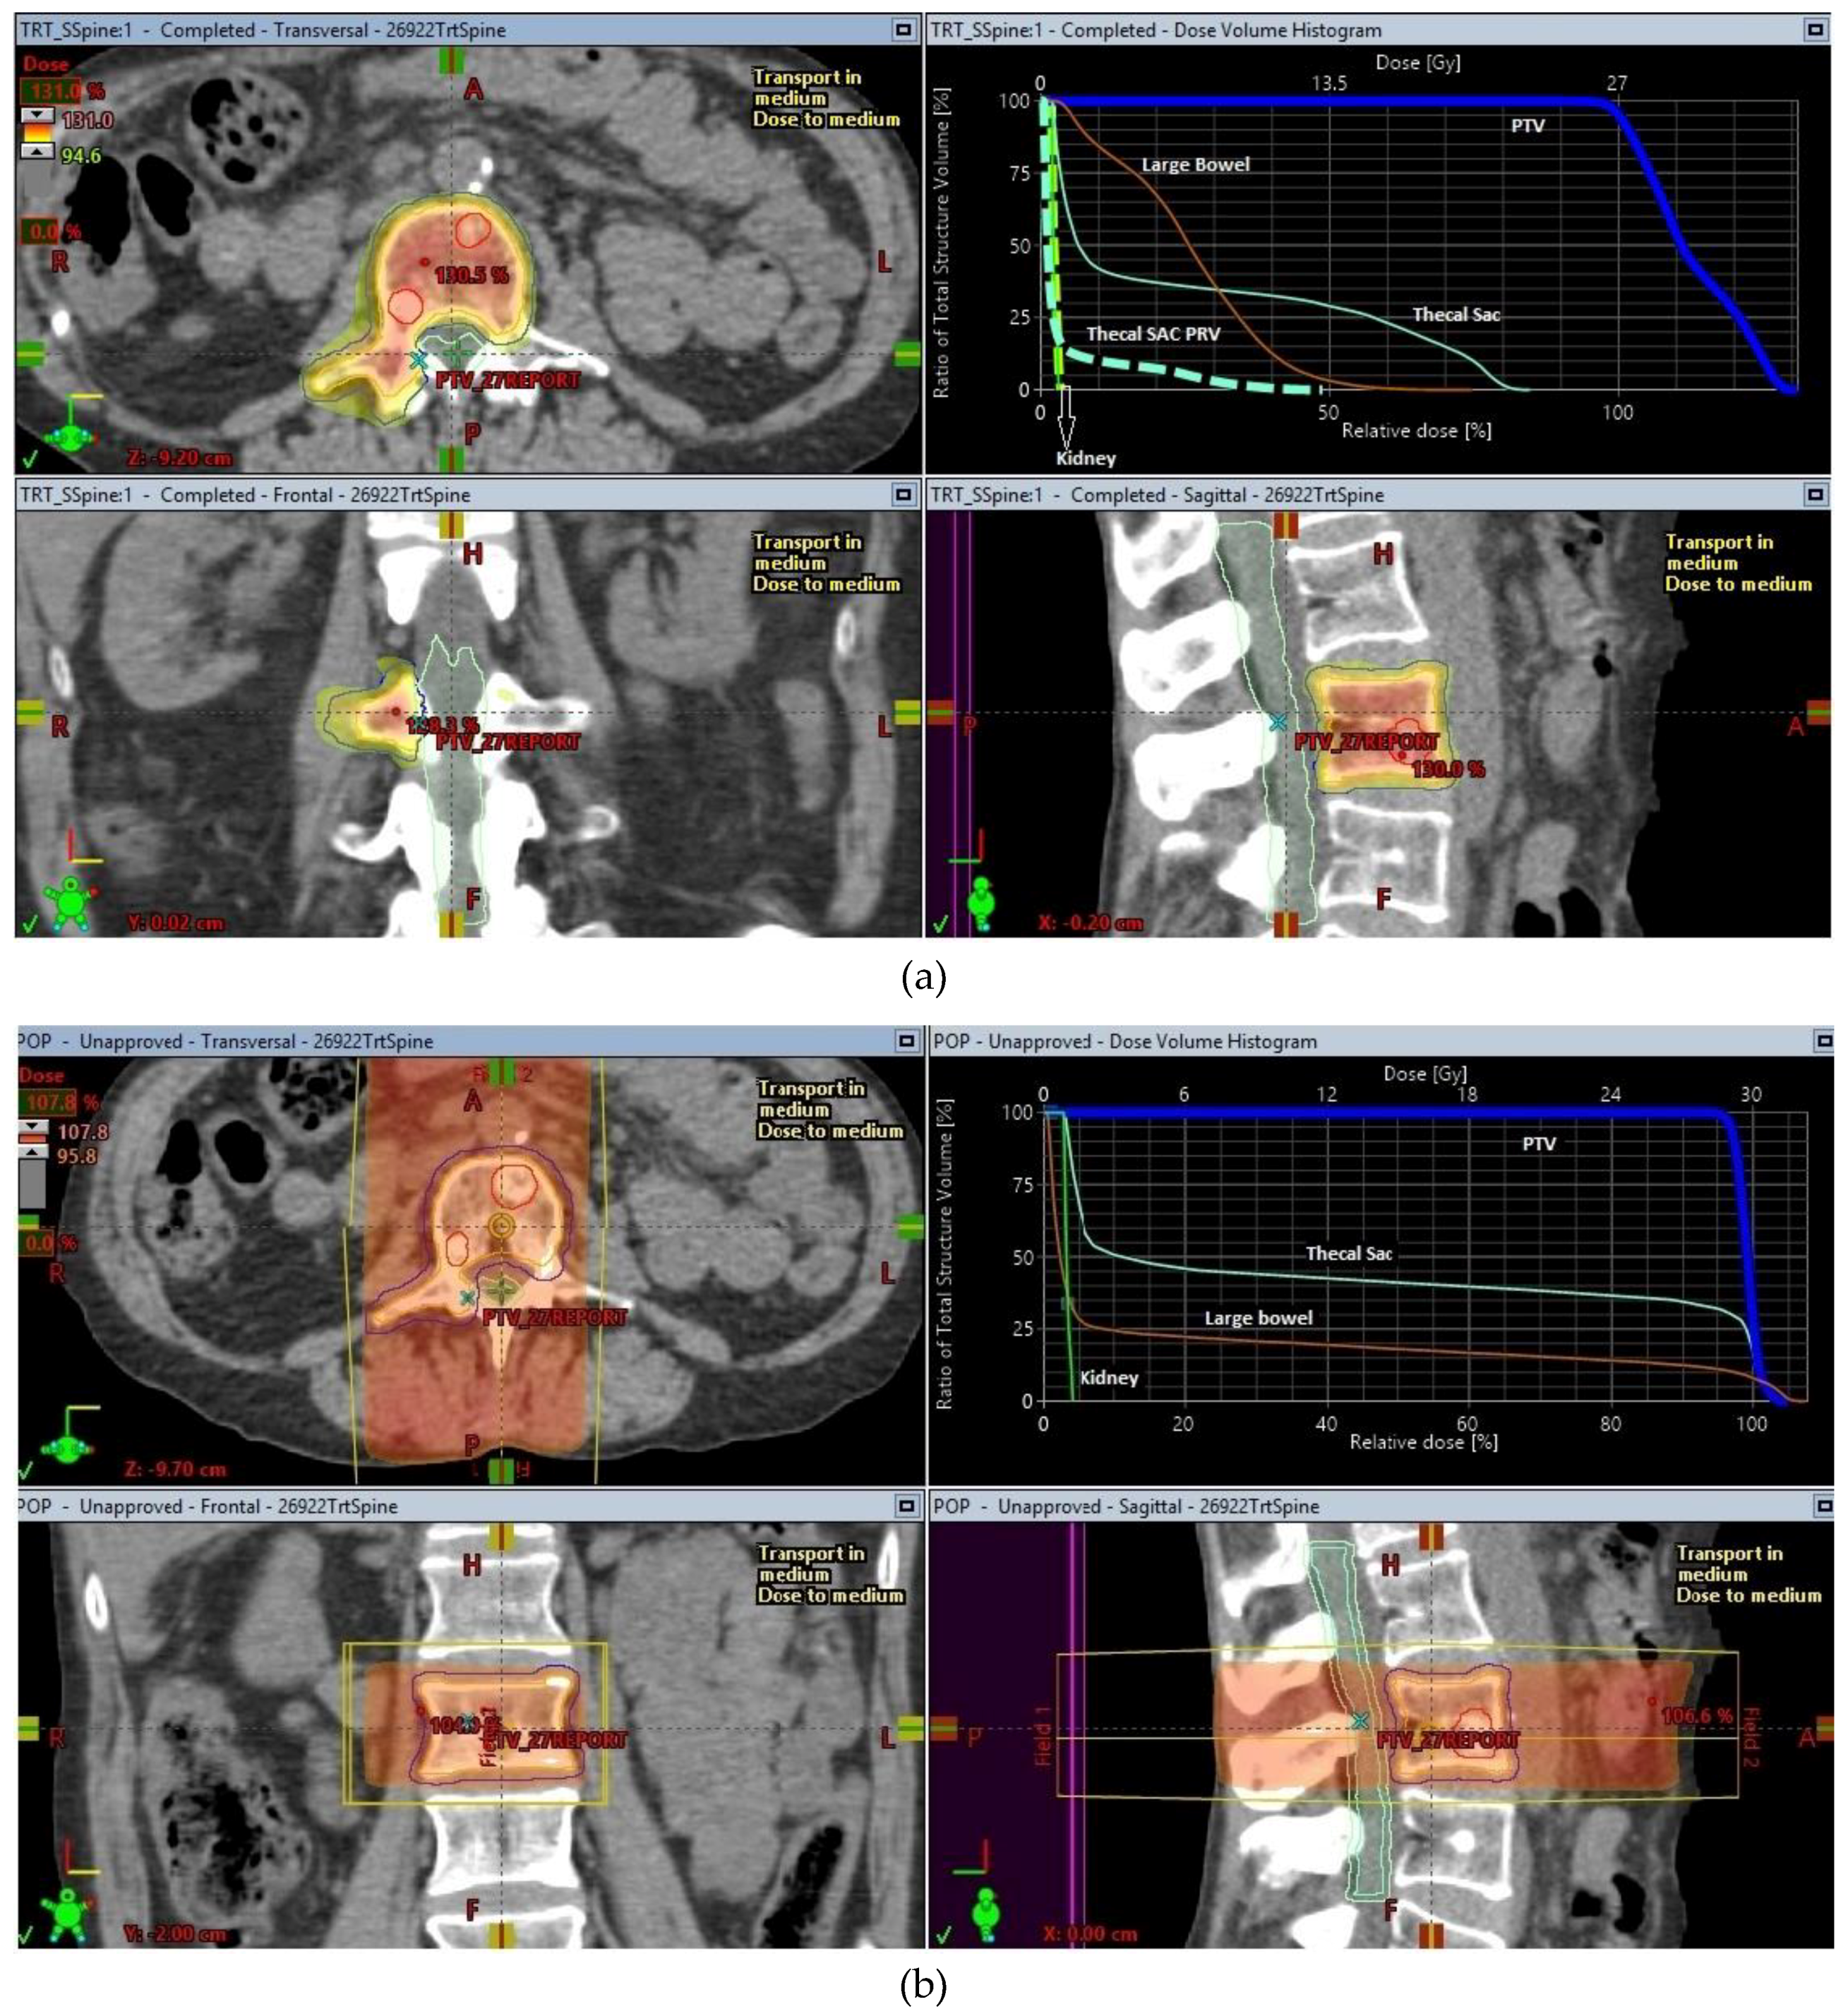

| Spine metastases | 24 or 27 | 2 or 3 |